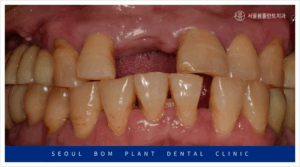

환자분께서는 50대 초반의

남성분으로 타 치과에서 했던

오른쪽 위턱 첫 번째 앞니(#11)의

임플란트가 빠져 상담을 위해

내원해 주셨는데요.

앞니는 원래도 잇몸뼈가 얇은 데다가

환자분께서는 임플란트 주위염으로 인해

잔존 잇몸뼈가 약해져

기존 임플란트가 탈락한 상황이었는데요.